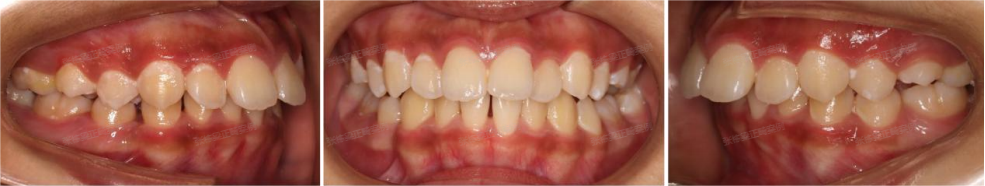

可以看到佩戴4个月的时候,孩子的牙齿和面型有了不错的变化,上下颌牙套贴合,双侧兔子皮筋二类牵引佩戴良好。

牙齿矫正14个月后,上下颌中线对正,上下牙齿排列整齐,牙弓卵圆形,上下牙弓匹配,前牙达到正常覆合覆盖,牙齿尖窝关系良好。